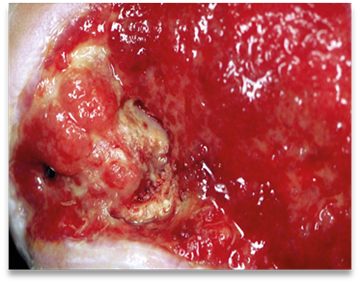

• the tissue quality. Are there signs of granulation or necrosis?

• signs of infection

The following chart describes the different types of exudate. The wound’s exudate gives you important information about the wound’s health. If you notice an unexpected change in exudate characteristics, this may mean that there is a change in the wound’s status, e.g that the wound is infected. If this happens, you should re-evaluate the wound as quickly as possible.4, 3